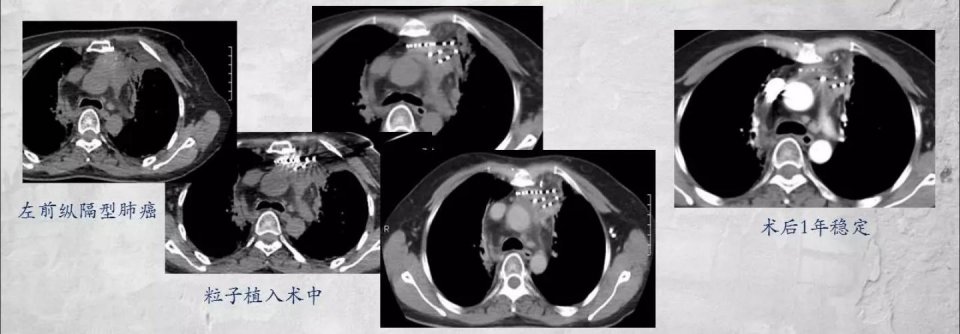

如下图这位42岁的女士,左侧纵隔型肺癌,没有手术条件,采用放射性粒子植入治疗,术后1年病情稳定。

此类晚期肺癌的病例中,获得较长生存期的也真不少。